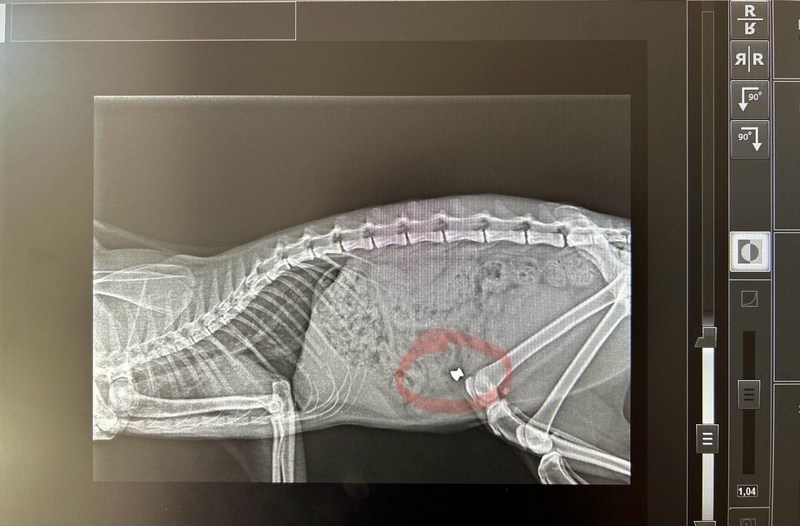

La situazione è estremamente preoccupante, con alcuni gatti che sono stati uccisi e solo due sono riusciti a salvarsi grazie all’intervento tempestivo di un veterinario. Una foto della lastra mostra chiaramente il proiettile nel gatto prima che venisse operato e salvato dal medico veterinario Prof. Gianni Marinacci di Rende.